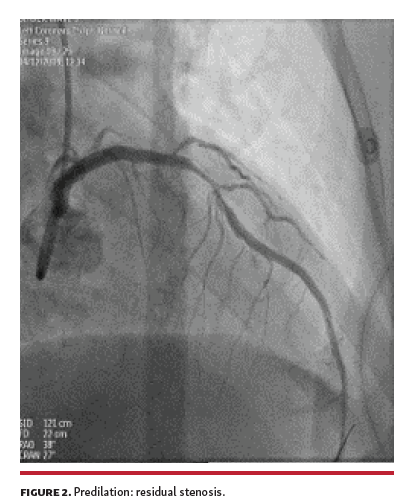

After several attempts with 2.0 x 15 mm and 2.5 x 15 mm compliant and non-compliant balloons used for predilation, a significant residual stenosis remained (Figure 2). At that time, we decided to use Shockwave intravascular lithotripsy (IVL; Shockwave Medical). A 3.00 x 12 mm lithotripsy balloon was chosen, but proved too bulky to advance and deliver. Guide-extension catheter improved support, and 4 cycles of lithotripsy were delivered, achieving full expansion (Figure 3). Subsequently, a 3.0 x 24 mm drug-eluting stent was delivered and deployed, with an optimal result (Figure 4).